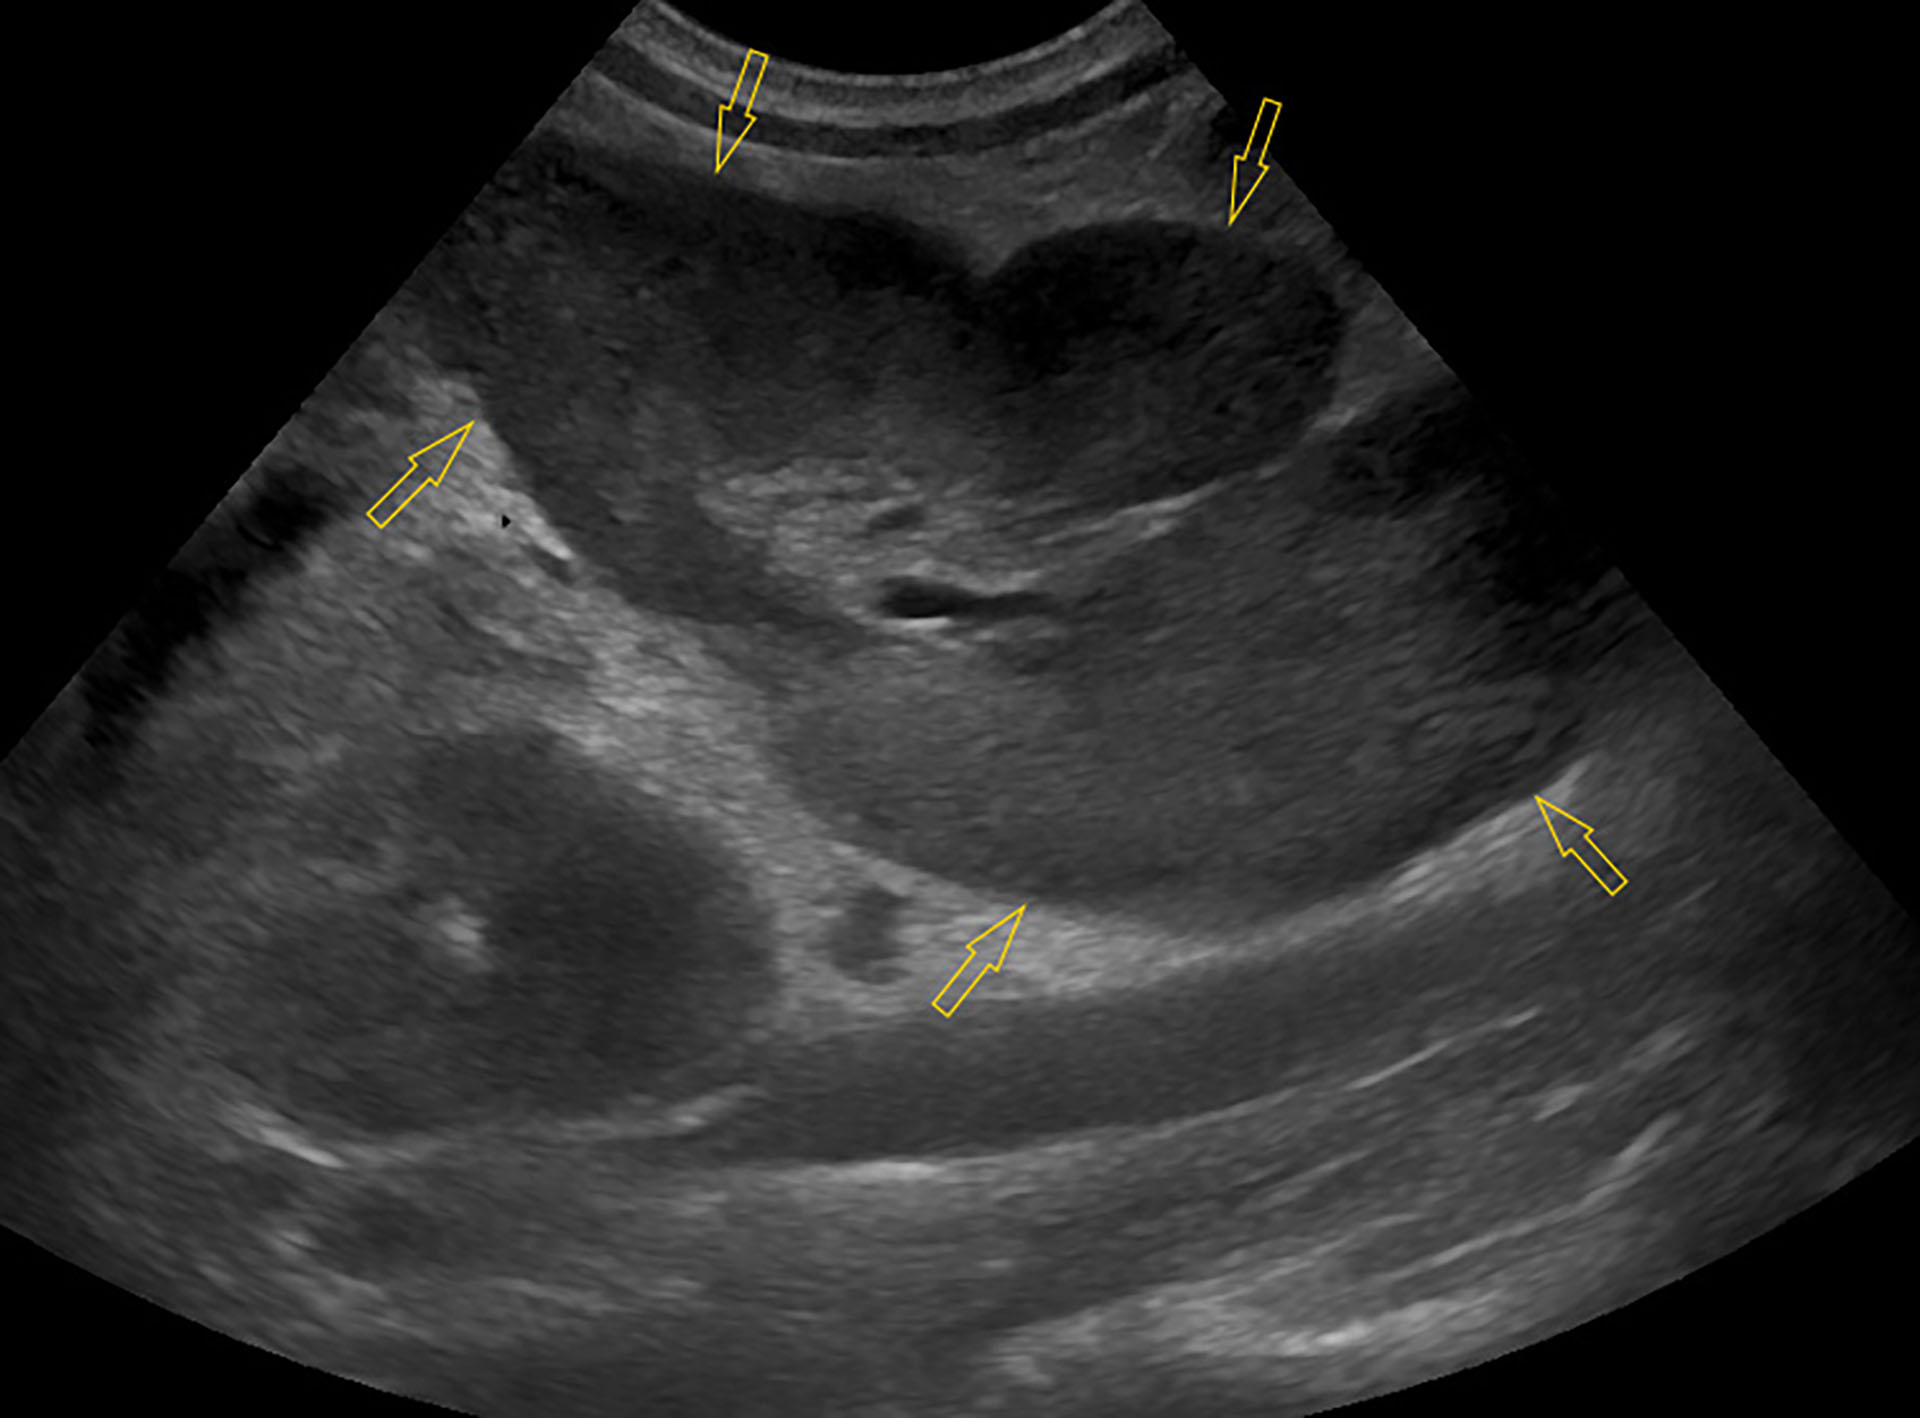

Figur 3. Ultralyd av en hypoekkogen og svært forstørret mesenteriell lymfeknute (avgrenset med gule piler).

Foto: Maria Hære

Ultralyd avdekket enorme mesenterielle lymfeknuter distribuert på en slik måte at de knapt kunne skilles fra hverandre (Figur 3). Alle lymfeknutene var heterogene med hypo- til anekkogene foci i parenkymet. Det var små anekkogene væskelommer i det ellers hyperekkogene omkringliggende krøset, samt kranialt for urinblæren. Resterende bukorganer, hadde normalt ultrasonografisk utseende.